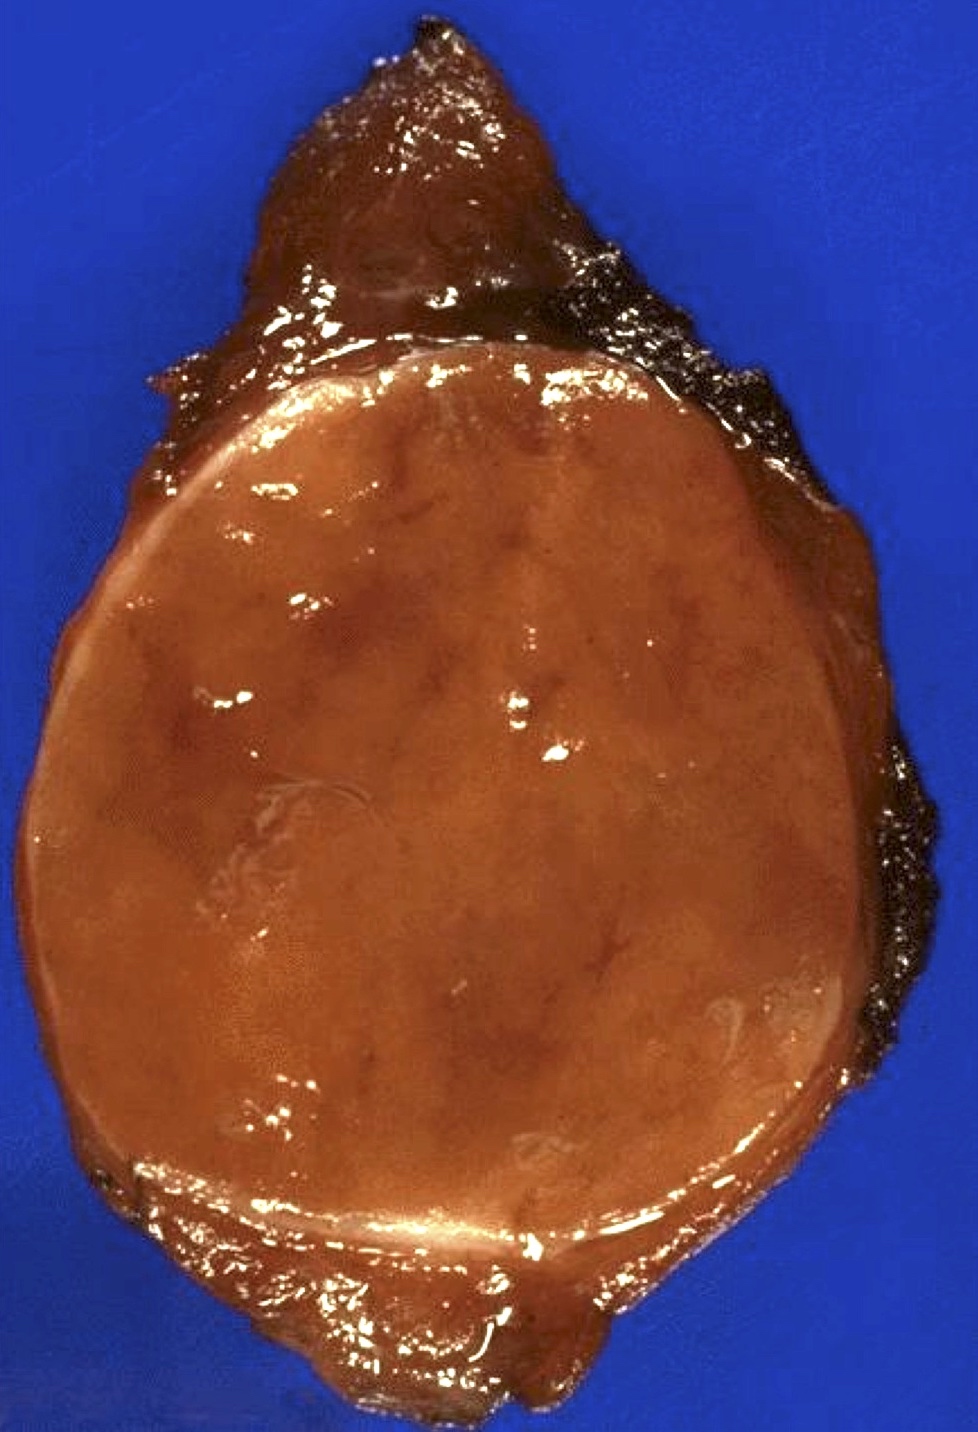

Gross description

- Solitary, encapsulated nodule; multiple if familial

- Variable size (1 - 10 cm)

- Solid, gray-white, tan to light brown

- Secondary changes: hemorrhage, cystic change, fibrosis, calcification, infarction; may develop post-fine needle aspiration cytology

- Rarely black; especially seen with minocycline therapy

Gross images

Contributed by Andrey Bychkov, M.D., Ph.D., Mark R. Wick, M.D. and AFIP

Images hosted on other servers: